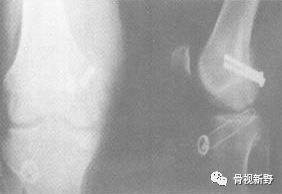

医源性Hoffa骨折见于膝关节ACL重建术。如果骨隧道位置太靠后或较小的股骨放置较粗的韧带,则有导致Hoffa骨折的潜在危险。

关节镜微创入路

关节镜微创手术可减少软组织剥离和出血量,术后关节功能及软组织恢复较好。但目前仅有少数个案报道,尚并无充分证据支持关节镜辅助Hoffa骨折。